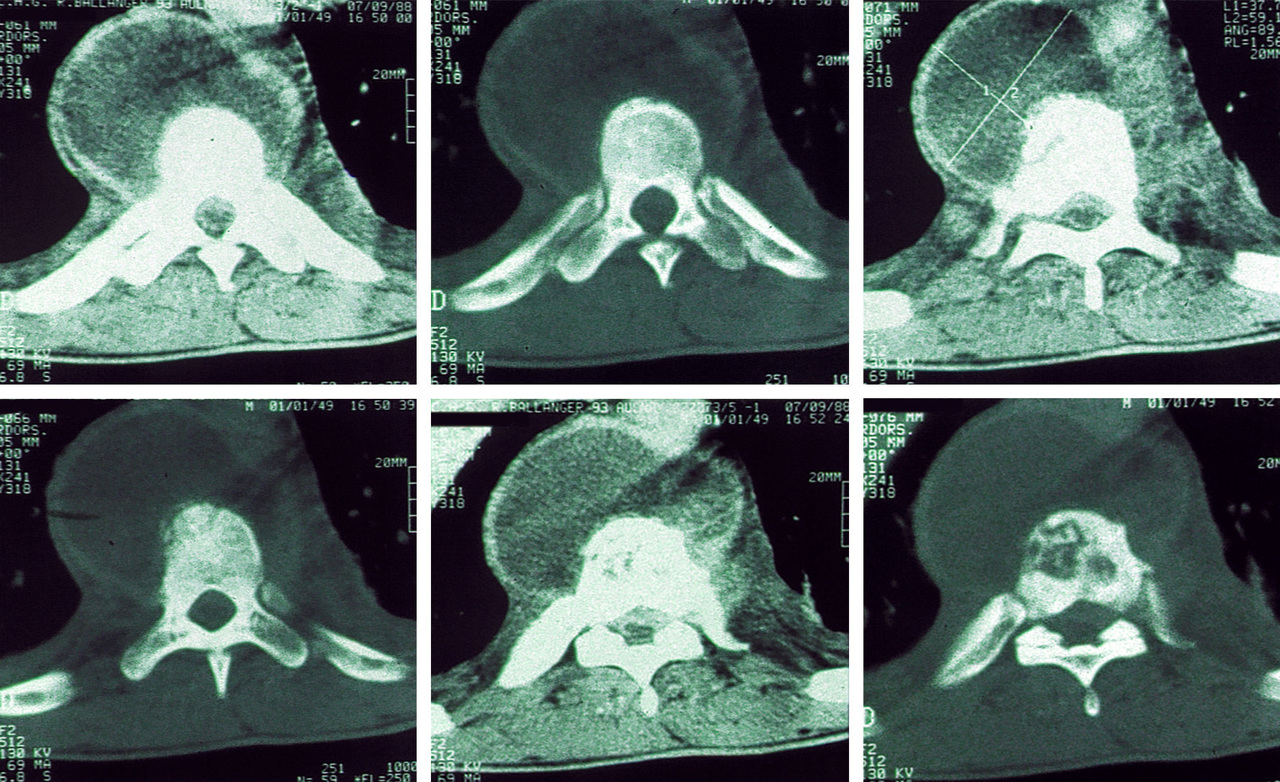

Scanner dorsal. Volumineux abcès paravertébral dans le cadre d'un mal de Pott dorsal.